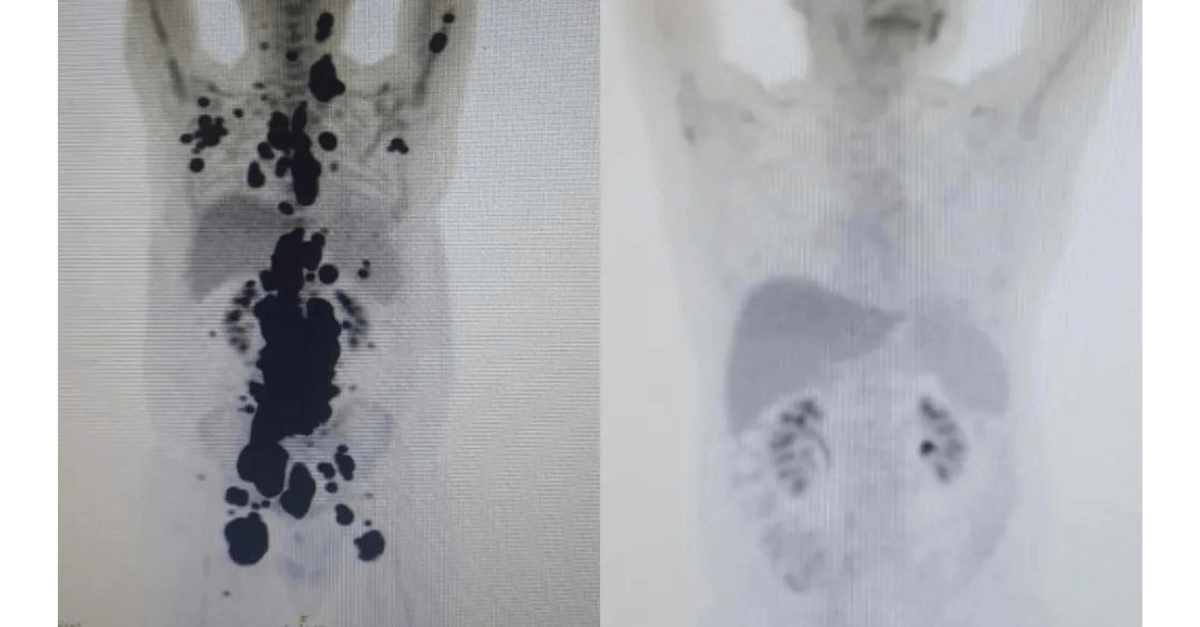

“Foi uma resposta muito rápida. Fico até emocionado (ao ver as duas ressonâncias de Paulo). Fiquei muito surpreso de ver a resposta, porque a gente tem que esperar pelo menos um mês depois da infusão da célula. Quando a gente viu, todo mundo vibrou. Coloquei no grupo de professores titulares da USP e todo mundo impressionado de ver a resposta que ele teve”, comemorou o especialista.